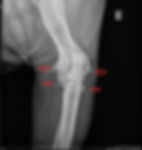

Die Diagnose erfolgt in der Regel durch eine gründliche klinische Untersuchung, bei der der Tierarzt die betroffenen Gelenke abtastet und den Bewegungsumfang testet. Häufig werden zusätzlich Röntgenaufnahmen gemacht, um den Zustand der Gelenke zu überprüfen.